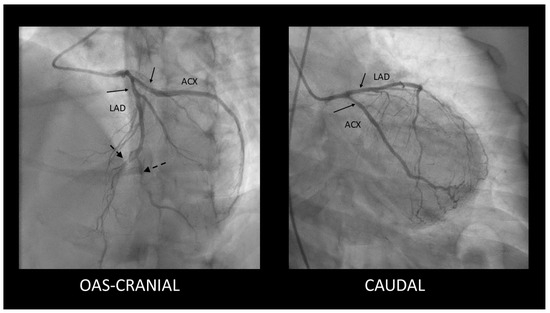

Spontaneous Coronary Artery Dissection Involving the Left Main with Extension to Left Anterior Descending Artery and Left Circumflex Artery: Diagnostic and Management Challenges